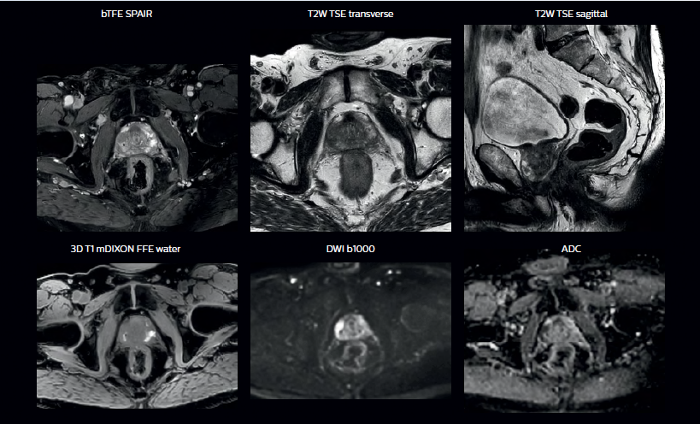

Grâce à un contraste des tissus mous supérieur à celui de la TDM, l’IRM offre une visualisation exceptionnelle des limites tumorales et de la proximité des structures critiques avoisinantes.

La possibilité de régler les contrastes peut fournir des informations encore plus précieuses sur les caractéristiques et l’étendue de la tumeur afin d’en faciliter la délimitation et offrir également des possibilités de stratégies d’augmentation de dose.

En plus de l’imagerie anatomique, l’IRM permet d’obtenir des informations fonctionnelles utiles pour la détection et la délimitation des tumeurs, ainsi que pour le suivi de la réponse au traitement.

Les images pondérées en diffusion (DWI), par exemple, permettent de distinguer des zones d’intensité de signal élevée dans les tissus mous qui indiquent la mobilité réduite de l’eau (c-à-d. la diffusion) d’une tumeur et peuvent également être utilisées pour identifier des ganglions lymphatiques. Les modifications du coefficient de diffusion apparent (ADC) du tissu ou de la lésion peuvent fournir des informations permettant de prédire la réponse de la tumeur à la radiothérapie.